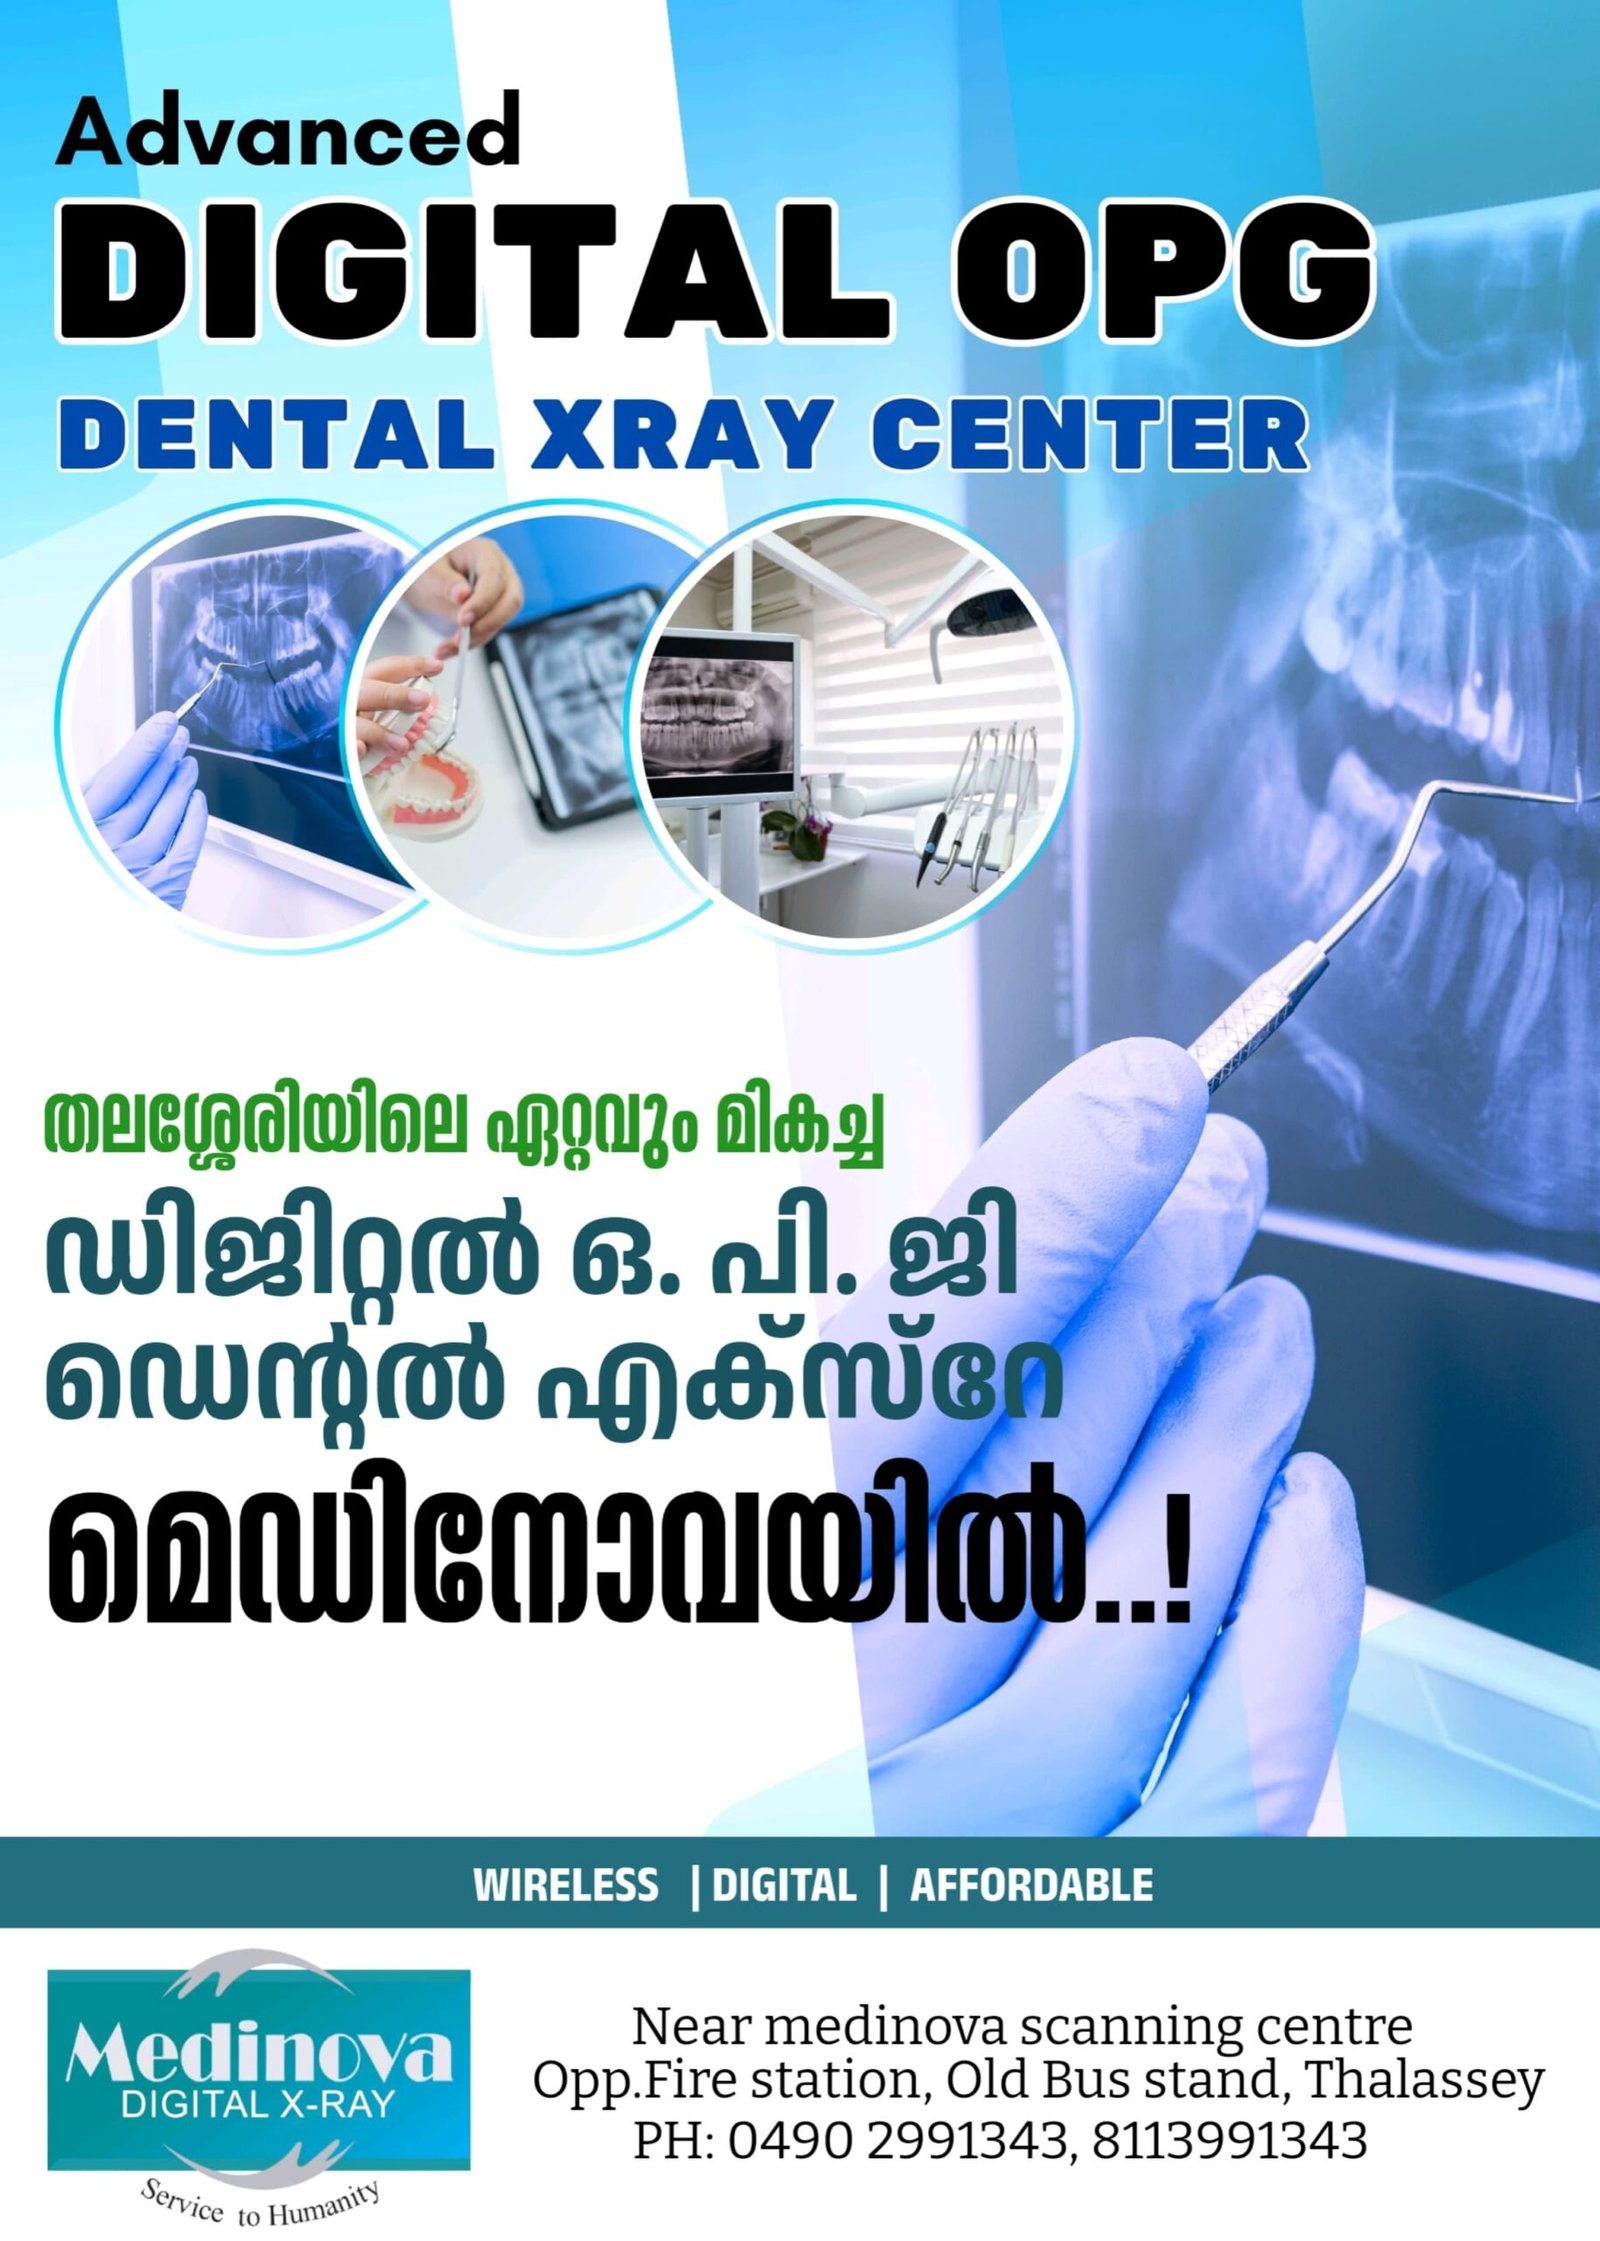

DIGITAL X-RAYS

Advanced Digital X-Ray Imaging for Precise Diagnostics

Experience the clarity and accuracy of our digital X-ray services, providing fast and precise imaging to support your healthcare needs. Utilizing the latest in digital technology, our skilled team ensures high-quality diagnosis with minimal exposure, all in a safe and comfortable setting.